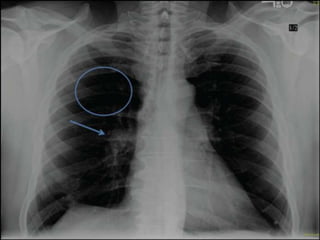

Silhouette Sign

• The loss of the lung/soft tissue interface due to the

presence of fluid in the normally air-filled lung

• If an intrathoracic opacity is in anatomic contact

with a border, then the opacity will obscure that

border

• Commonly seen with the borders of the heart,

aorta, chest wall, and diaphragm

Silhouette Sign • Theloss of the lung/soft tissue interface due to the presence of fluid in the normally air-filled lung • If an intrathoracic opacity is in anatomic contact with a border, then the opacity will obscure that border • Commonly seen with the borders of the heart, aorta, chest wall, and diaphragm

• #5 For the heart, the silhouette sign can be caused by an opacity in the RML, lingula, anterior segment of the upper lobe, lower aspect of the oblique fissure, anterior mediastinum, and anterior portion of the pleural cavity. This contrasts with an opacity in the posterior pleural cavity, posterior mediastinum, of lower lobes which cause an overlap and not an obliteration of the heart border. Therefore both the presence and absence of this sign is useful in the localization of pathology.

• #6 For the heart, the silhouette sign can be caused by an opacity in the RML, lingula, anterior segment of the upper lobe, lower aspect of the oblique fissure, anterior mediastinum, and anterior portion of the pleural cavity. This contrasts with an opacity in the posterior pleural cavity, posterior mediastinum, of lower lobes which cause an overlap and not an obliteration of the heart border. Therefore both the presence and absence of this sign is useful in the localization of pathology. NON VISUALISATION OF THE BORDER OF AN ANATOMICAL STRUCTURE NORMALYY VISUALUSED SHOWS THAT THE AREA NEOGHBOURING THE MARGIN IS FILLED WITH TISSUE OR MATERIAL OF THE SAME DENSITY EXAMPLE ; OBILLTERATION OG THE LEFT HEART BORDER DUE TO MIDDLE LOBE ATELECTASIS . RULE CAN ALSO BE APPLIED TO THE ARCH OF AORTA HEMIDIAPHGRAMS AND LEFT BORDER OF THE HEART.